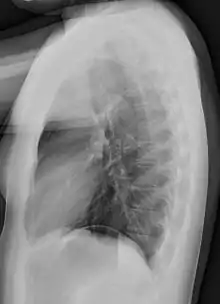

Gallery

Projectionally rendered CT scan, showing the transition of thoracic structures between the anteroposterior and lateral view